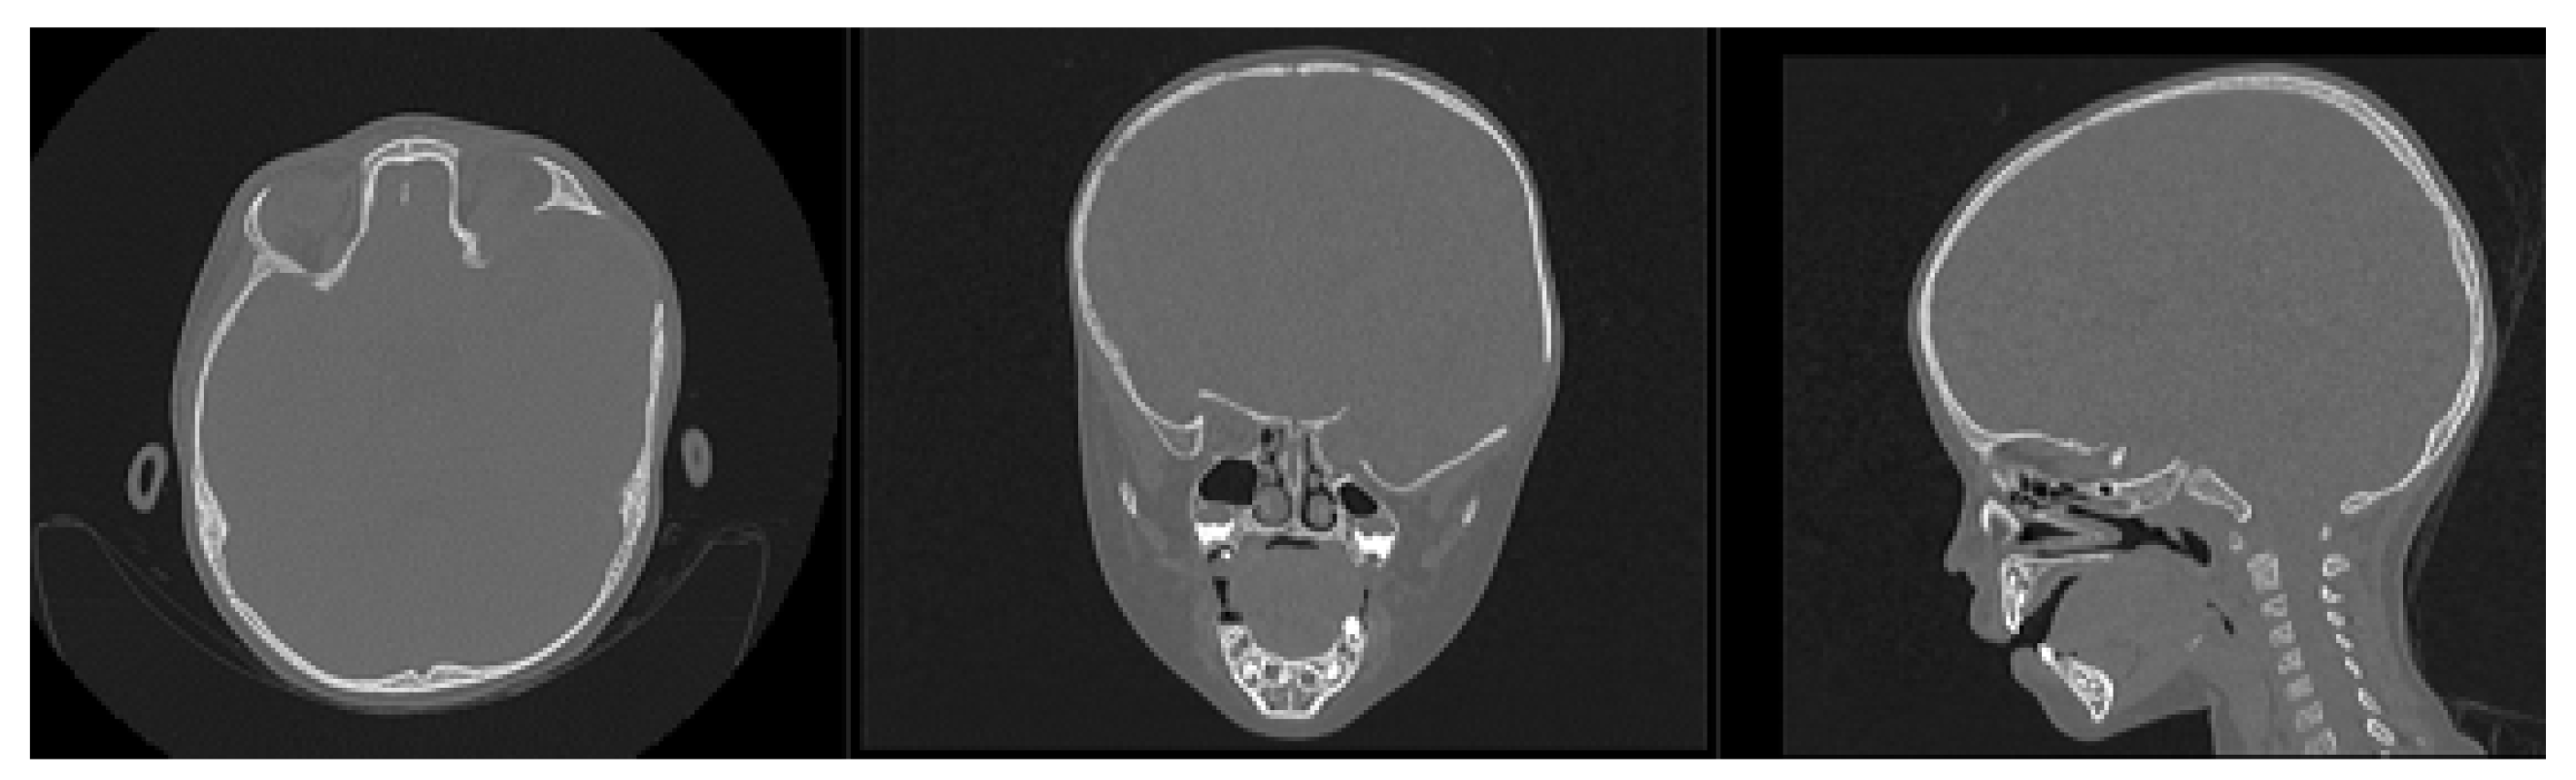

3.7.1. Diagnosis and Analysis

3.7.2. Surgical Planning